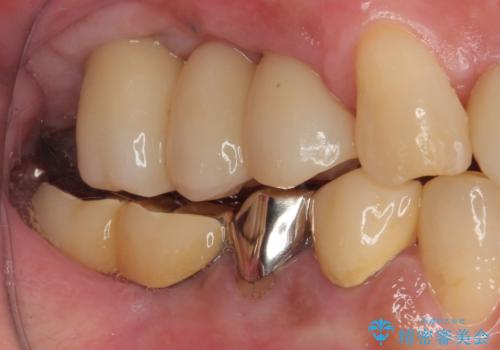

抜歯即時埋入インプラントによる補綴治療の特徴は、短期間であることや処置数が少ないことが挙げられます。また、表側の歯肉の陥凹を避けることができるというメリットがあります。しかしながら、今回は歯根破折の程度が酷く、やや膨らみを失うこととなりましたが、スムーズに治療を終えることができました。

臼歯部は前歯以上に炎症が酷く、抜歯即時埋入不可と判断されましたが、従来法よりは短期間で終えることができました。